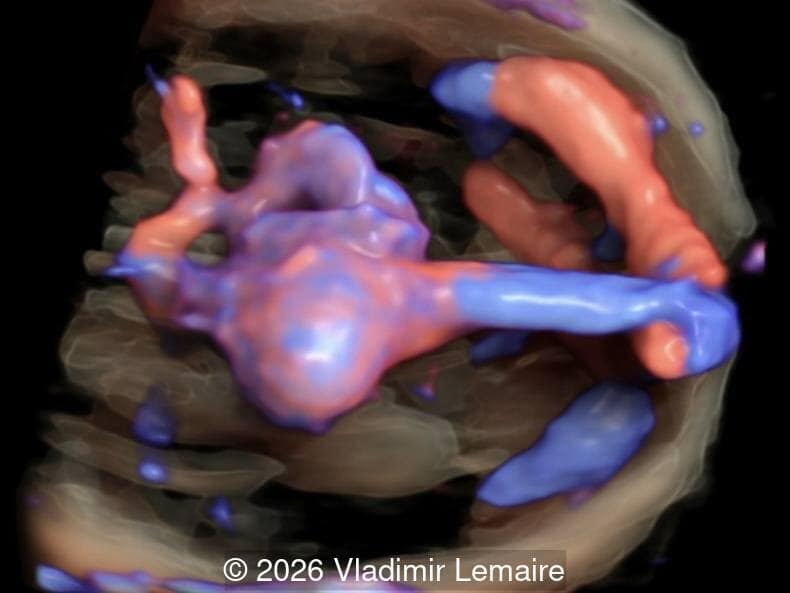

Axial 3D glass-body mode of the intracerebral vasculature.

Image 2 Axial 3D glass-body mode of the intracerebral vasculature.

Our imaging revealed enlargement of the fetal heart with dilation of the superior vena cava. On further evaluation, we identified an elongated anechoic cystic structure in the midline of the head, without mass effect on the surrounding structures. Color doppler demonstrated an arteriovenous fistula between the deep choroidal arteries and the embryonic median prosencephalic vein of Markowski. The vein of Galen aneurysmal malformation was likely the contributing factor to the cardiac enlargement. Cardiac function was, however, preserved and hydrops not present. Additional images are shown below.

We present a case of Vein of Galen Aneurysmal Malformation (VGAM).